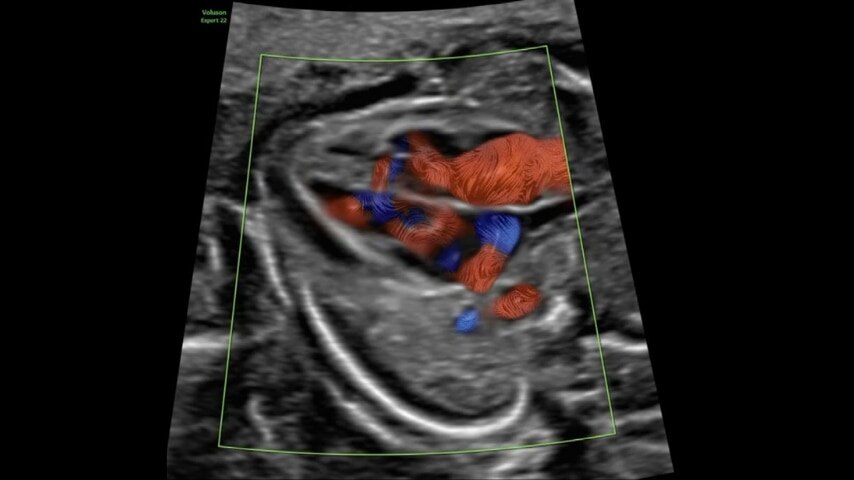

Voluson™ Graphicflow

Visualize trajectories of fetal blood cells in real-time

Provides a graphical representation of the trajectories of the blood cells in real-time to visualize complex blood flow quickly and clearly, helping to differentiate normal from abnormal hemodynamics especially in fetal heart and fetal brain.